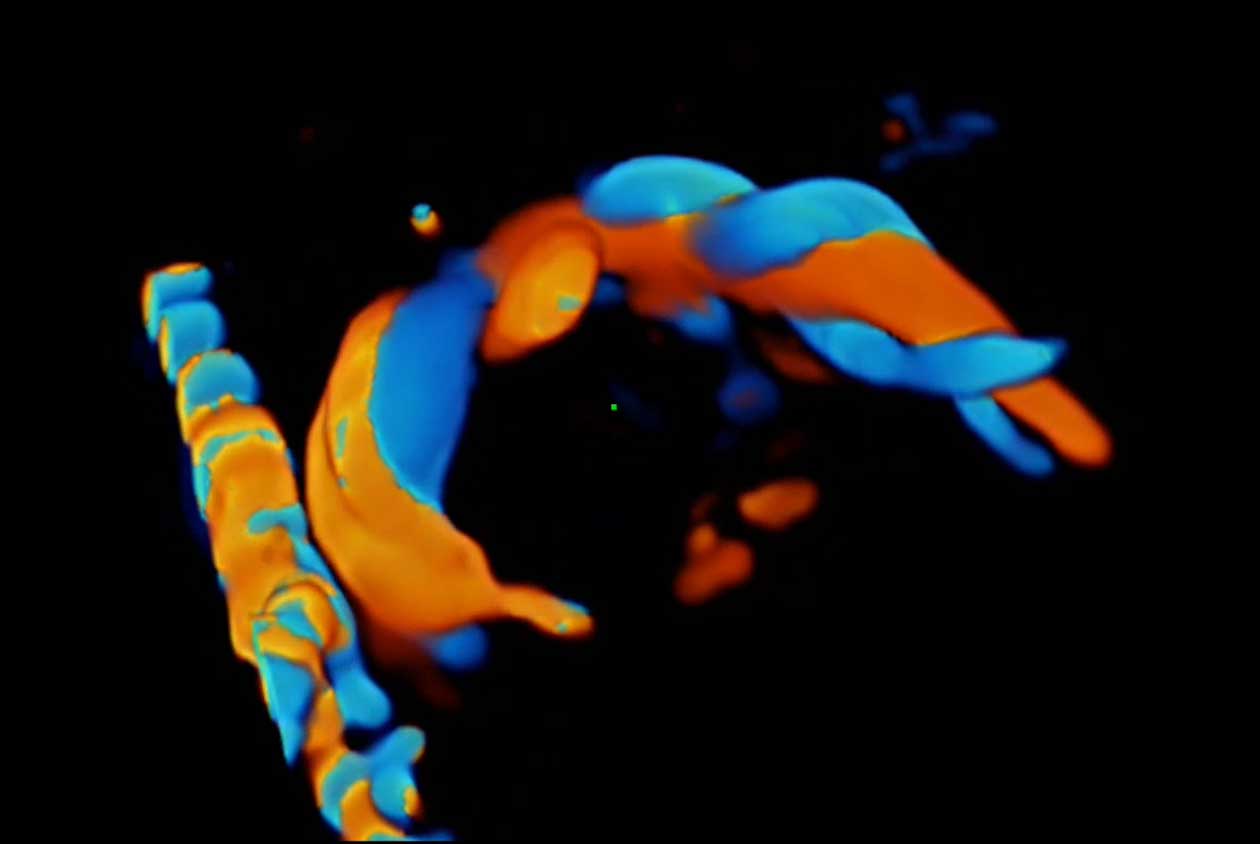

Women's Health | Radiology | Cardiovascular Imaging

Advanced Technologies

Enhancing Clinical Certainty

Clinical Images